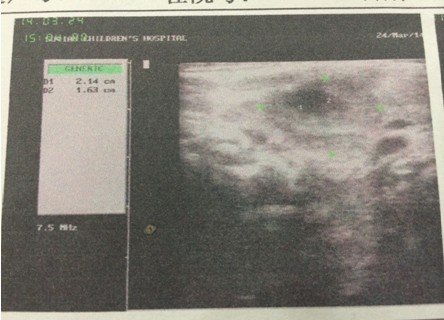

4个月大的婴儿,右颈部耳垂下方(2公分左右)有个硬疙瘩,婴儿无明显异常,吃奶睡觉等等一切正常,精神 状态很好,挂了3天的消炎水,图片为在2家医院做的B超,求解这个疙瘩是什么,需要怎么样治疗。医生叫继续挂消炎水进一步观察!(备注:B超2描述是:右侧颈部肌层后方探及22*15mm不均质低回声包块,其周围可见数枚低回声结节。 超声印象:右颈部包块伴周围淋巴结肿大。) 点击展开 匿名用户 2014-03-24 19:47 为您推荐: 其他回答 病情分析: 这个情况考虑是属于增生的症状, 指导意见: 你好,目前这个问题我建议及时消炎治疗,继续观察吧。 白其雨_6xwx 2014-03-24 21:36 相关问题 大夫您好我脖子右侧耳垂下方6公分左右 十五个月的宝宝耳垂前边脸颊上长了个长了个小疙瘩是怎么回事 十五个月的宝宝耳垂前边脸颊上长了个长了个小疙瘩是怎么回事

状态很好,挂了3天的消炎水,图片为在2家医院做的B超,求解这个疙瘩是什么,需要怎么样治疗。医生叫继续挂消炎水进一步观察!(备注:B超2描述是:右侧颈部肌层后方探及22*15mm不均质低回声包块,其周围可见数枚低回声结节。 超声印象:右颈部包块伴周围淋巴结肿大。)